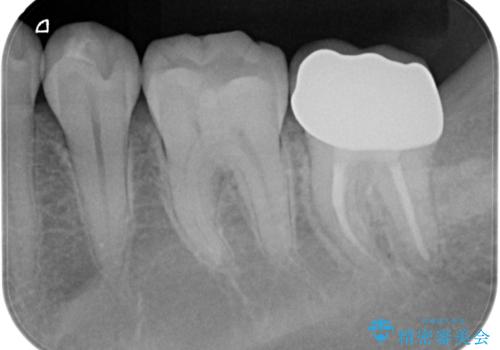

他院での治療に不信感 虫歯除去後のジルコニアクラウン

- 歯が痛くなり、他院で治療してもらったところ不信感があり、当院に受診に来られました。

神経をとる処置をされた形跡がありましたがまだ虫歯が残っていたので全て取り除き、壁を立てて根管治療ができる状態にして、根管治療・ジルコニアクラウンで治療を行いました。

虫歯除去、根管治療は拡大鏡やマイクロスコープを用いて治療を行っています。